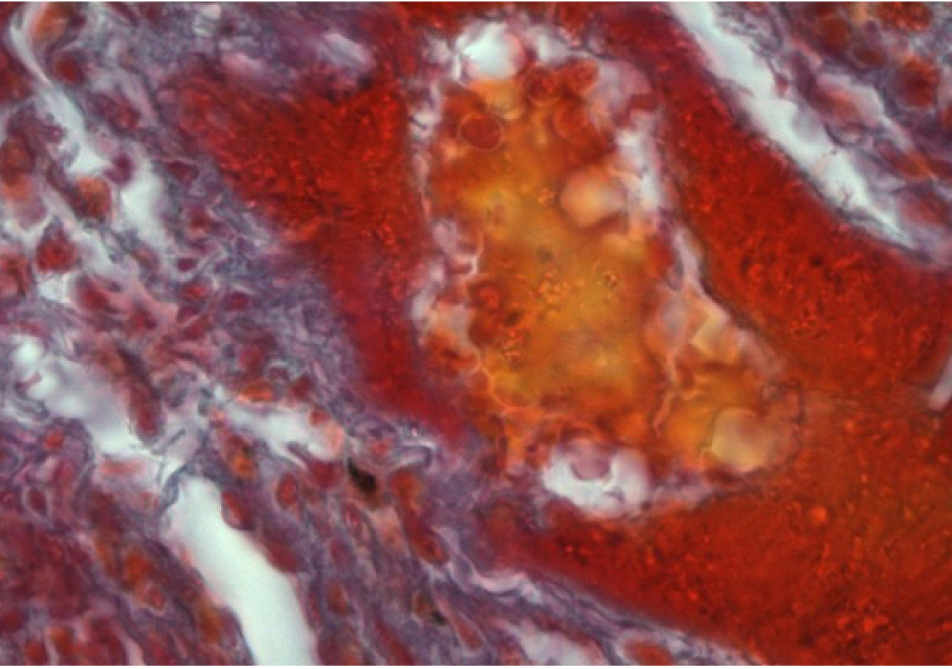

Наблюдается активизация фибробластов, окруженных пучками коллагеновых волокон (рис. 3, 4).

Рис. 4. Образование коллагеновых волокон в стенке сосуда. Окраска по Массону. Ок. 10. Об. 100. Иммерсия